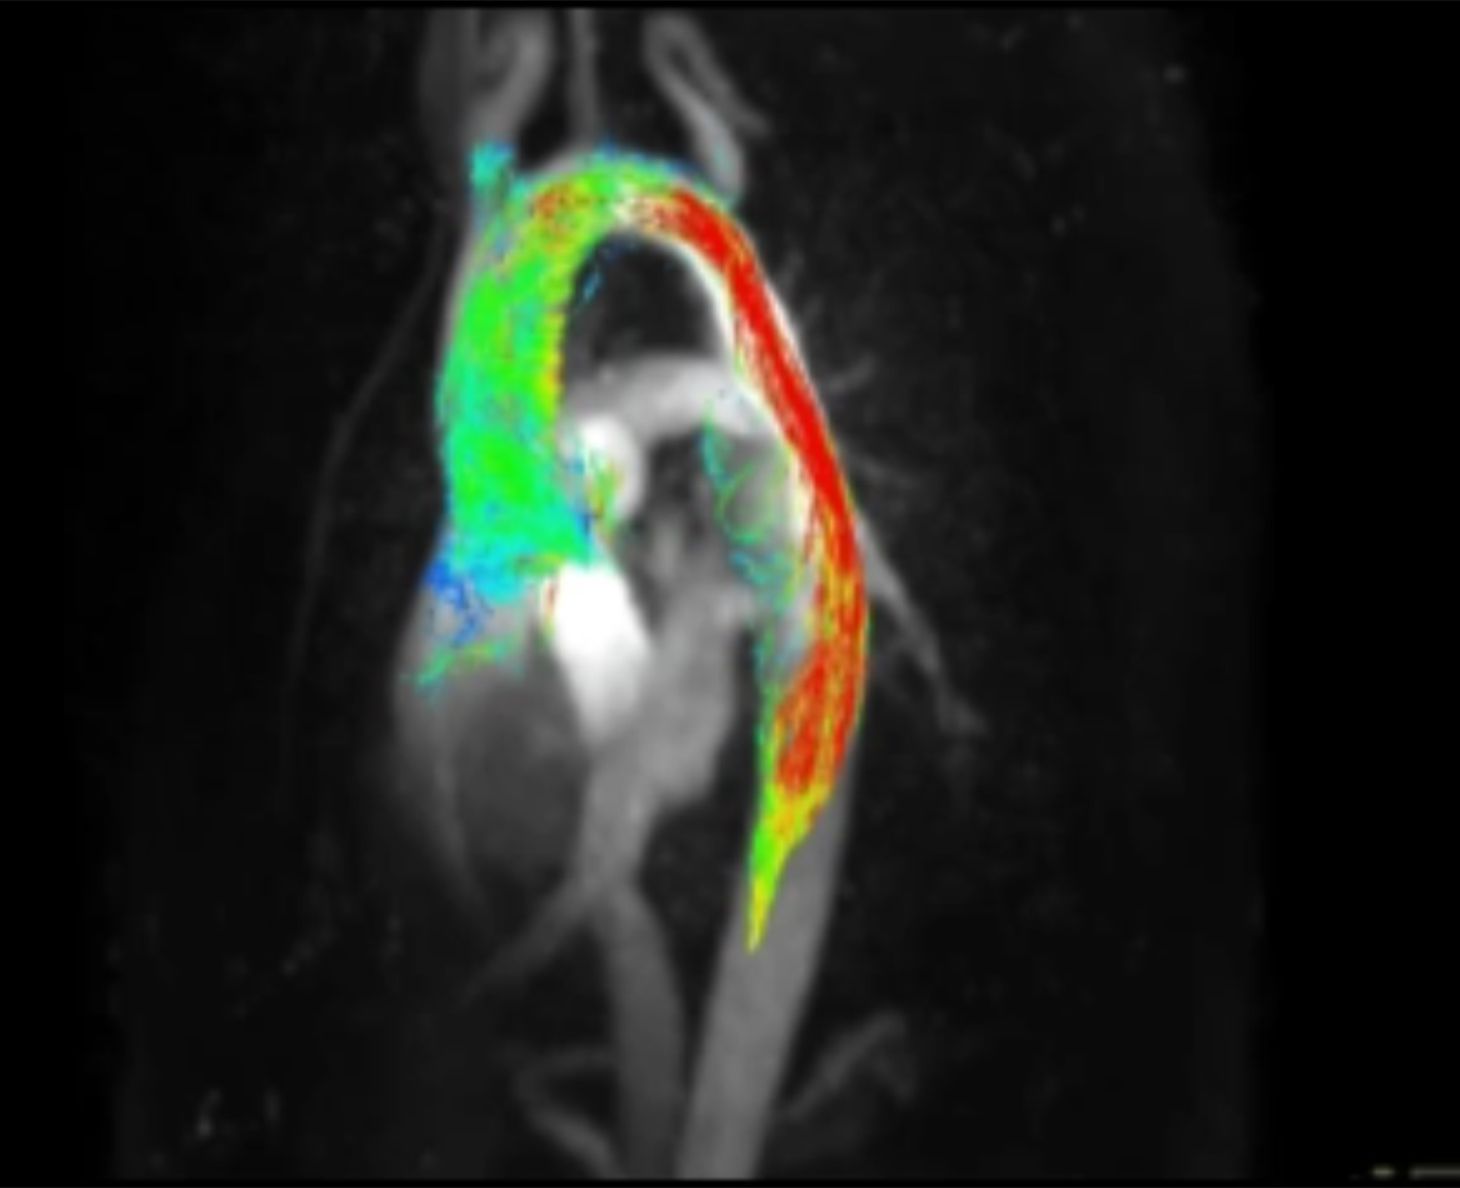

4-dimensionale Flussmessungen, die den Blutfluss neben einer 3-dimensional-räumlichen Aufnahme zusätzlich über die Zeit (4. Dimension) darstellen. Turbulente Strömungen und weitere physikalische Berechnungen können mit dieser modernen Forschungssequenz erfolgen.

Ansprechpartner: Dr. med. Anja Hanser